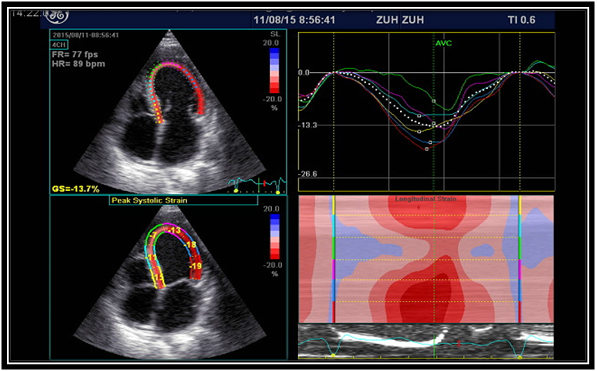

Two consecutive heart cycles at rest, from the three standards apical planes (four-chamber, two-chamber, and long-axis), were considered by conventional 2D gray scale echocardiography. In each of the apical views, the endocardial contour was manually drawn and tracking of deformation was automatically performed by the software, once visual confirmation of good quality tracking was given by the operator. The software algorithm automatically segmented the LV into six equidistant segments and selected suitable speckles in the myocardium for tracking. The software algorithm then tracked the speckle patterns on a frame by frame basis using the sum of absolute difference algorithm. Regional longitudinal peak systolic strain (RLS) was measured in all views between aortic valve opening and closing for the 6 basal, 6 midventricular, and 4 apical segments and 17th segment was apical cap and averaged from the 17 segments to provide global longitudinal peak systolic strain (GLS)8 (Figure 1A & 1B).

Figure 1A: Left panel demonstrates apical four-chamber view. Corresponding strain curves are shown in the right panel. GLS is decreased with strain values of - 13.7 %.